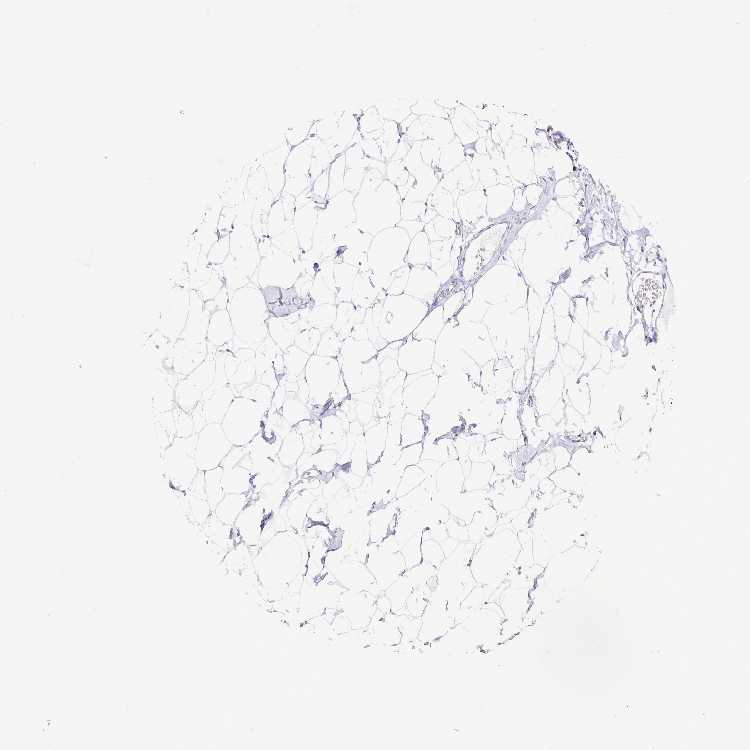

BREAST - Antibody stainingi

Antibody staining in the annotated cell types in the current human tissue is reported as not detected, low, medium, or high, based on conventional immunohistochemistry profiling in selected tissues. This score is based on the combination of the staining intensity and fraction of stained cells.

Each image is clickable and will lead to virtual microscopy that enables deeper exploration of all samples and also displays staining intensity scores, fraction scores and subcellular localization as well as patient and tissue information for each sample.

Antibody HPA038295Antibody HPA038296

Adipocytes Not detectedNot detected

Glandular cells Not detectedNot detected

Myoepithelial cells Not detectedNot detected